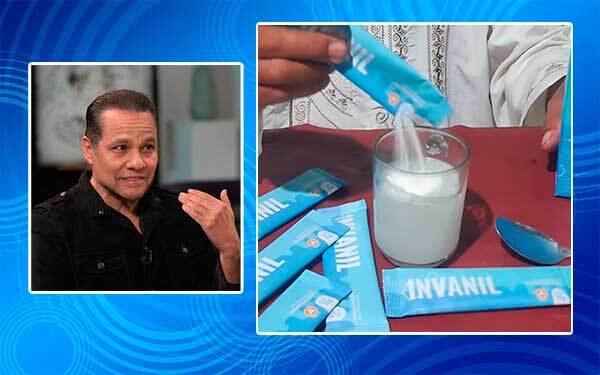

— Ceritakan kepada pembaca kami, apa nama produk Anda?

— Produk yang merupakan hasil dari puluhan tahun praktik medis saya ini bernama Invanil. Produk ini membantu menghilangkan nyeri dan rasa tidak nyaman pada sendi hanya dalam 4 hari, dan dalam waktu satu bulan mampu memulihkan kesehatan sendi bahkan pada kasus yang paling parah.

— Bagaimana cara kerja Invanil?

— Tidak ada hal ajaib dalam produk ini hanya sains dan hasil riset bertahun-tahun. Invanil mengandung 12 bahan aktif yang diformulasikan secara unik untuk merangsang proses regenerasi alami jaringan sendi. Karena terbuat dari bahan-bahan alami, produk ini tidak hanya bermanfaat untuk sendi, tapi juga untuk tubuh secara keseluruhan.

Cara penggunaannya juga sangat mudah: cukup larutkan satu sachet ke dalam segelas air dingin, aduk hingga larut sempurna, lalu minum. Waktu terbaik untuk mengonsumsinya adalah sebelum tidur. Saat tubuh beristirahat di malam hari, produk ini bekerja secara perlahan dengan mengurangi peradangan dan membantu proses regenerasi sel sendi dari dalam.